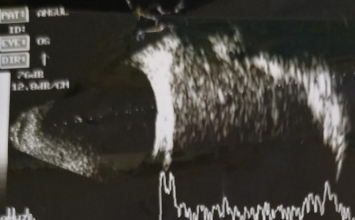

A one and half year-old boy visited Pediatric OPD with the complaints of low-grade fever, anorexia, abdominal distension, and weight loss for 15 days. His mother also complained of progressively increasing swelling of left eye for 5 days. On physical examination, patient was afebrile and moderate pallor was present. Per abdomen examination revealed non-tender, soft lump in right hypochondrium to right lumber quadrant up to midline. His weight was 7.2 kg (expected weight=12.2 kg) and height was 70 cm (expected height=87.8 cm). Ophthalmological examination revealed inferior globe dystopia and proptosis of left eye (Figure 1 and 2). Anterior segment was normal in both eyes. Fundus evaluation demonstrated choroidal folds in left eye, rest of the findings were normal in both eyes. UBM scan of left orbit showed large homogenous lesion superior to globe with mild to moderated spikes (Figure 3). The laboratory investigation revealed hemoglobin level 8g/dL, total leucocyte count 8,200/mm3, platelet count 32,500/mm3 and erythrocyte sedimentation rate 33.2mm in first hour. Twenty-four hour urinary vanilly-mandelic acid level was found to be elevated (68 µmol/mL; normal=0-10 µmol/mL). Bone marrow aspiration discovered infiltration with round cell indicative of neuroblastoma. Abdominal USG disclosed a large heterogeneously hypoechoic mass (78×30×24 cm in size) with multiple foci of calcification in right hypochondrium crossing midline causing mass effect and medially displacing aorta and inferior vena cava. Abdominal USG findings further supported by magnetic resonance imaging (MRI) which also revealed hepatic metastases. Contrast enhanced CT orbit findings reported a relatively well defined heterogeneously enhancing soft tissue mass lesion of size 32×25×27 mm in extraconal space of left orbit, possibly arising superolateral wall (frontal bone) of left orbit showing speculated/ ‘sun-ray’ periosteal reaction(Figure 4). Mass effect was evidenced by inferior and lateral displacement of left extra-ocular muscles, optic nerve, and eye globe with proptosis. USG guided true-cut biopsy of abdominal mass reveled neuroblastoma. Based on above-mentioned signs and investigations, child was diagnosed as a stage IVwith hepatic metastases and osseous metastatic lesion of left orbit. Department of Pediatric Oncology started chemotherapy (cisplatin, doxorubicin, etoposide, and ifosfamide) with injection ondansetron and injection ranitidine. On further following the child, he developed exposure keratopathy in affected eye(Figure 5). Unfortunately, child died while undergoing chemotherapy.

Figure 3. Ultrasound biomicroscopy scan of left orbit showing homogenous lesion superior to globe with mild to moderated spikes.